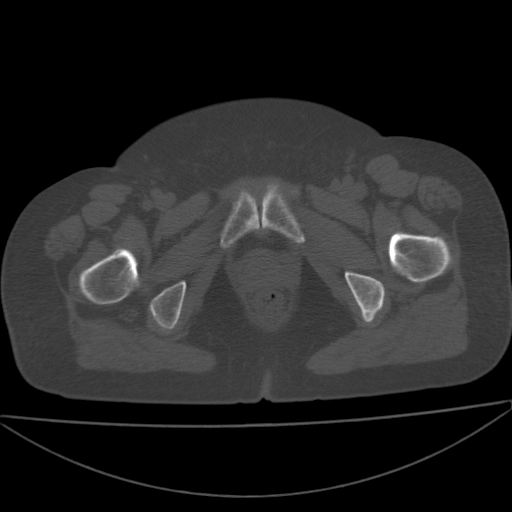

以下是引用余辉在2009-4-23 17:08:00的发言:[br]考虑右髋关节退行性变.股骨颈改变考虑陈旧性骨折可能,股骨头顶部关节面下似有透亮区,股骨头皮质环增厚,考虑有股骨头坏死

以下是引用王显瑞在2009-4-23 16:45:00的发言:[br]考虑股骨颈陈旧性骨折,股骨头缺血型坏死